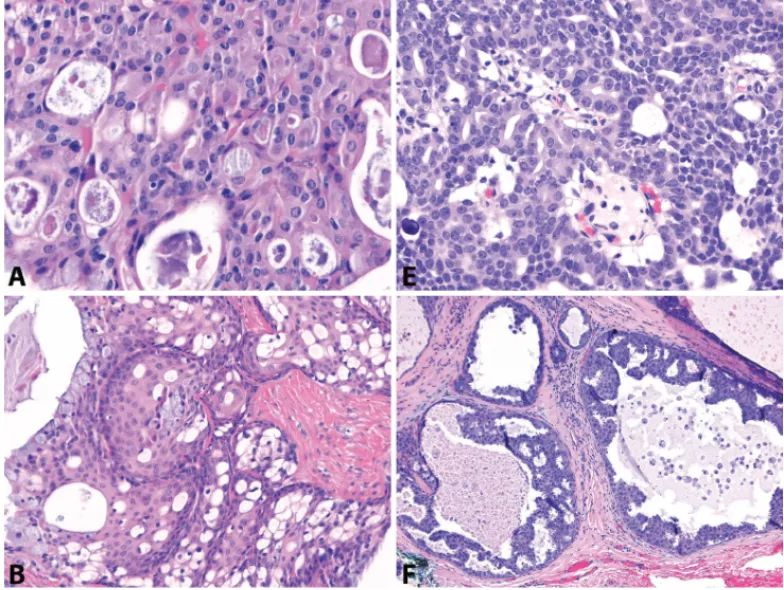

Figure 1: Mucoepidermoid carcinoma vs. Intraductal carcinoma. At high power, some mucoepidermoid carcinomas (A) and intraductal carcinomas (E) can show microcystic architecture. However, low power reveals more characteristic macrocystic and solid areas in mucoepidermoid carcinoma (B), and intraductal proliferation and intraluminal growth in intraductal carcinoma (F). Most mucoepidermoid carcinoma cells express p63 (C), while only the non-neoplastic peripheral cell layer is positive in intraductal carcinoma (G). These peripheral myoepithelial cells also express SMA (H). PAS-positive, diastase-resistant intracytoplasmic mucin vacuoles are present in mucoepidermoid carcinoma (D), but caution should always be exercised as mucinous metaplasia can occur in many other salivary gland tumors.